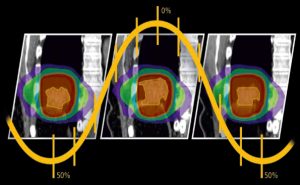

4D Binning

Tüm 4D işleme çalışmaları tek bir sistemde yapılabilir.

MIM Maestro’nun 4D binning özelliği, faz tabanlı ve genlik tabanlı binning işlerini otomatik yapabilir, böylece veri alma çalışma istasyonlarına duyulan gereksinim azalır. Otomatik kontur yayma özelliği, bir kapılı fazda yapılan konturlama işleminin bir dakikadan az bir sürede tüm kapılı fazlara deforme edilmesini sağlar. Sonra her bir kapılı fazda bulunan konturlar, tek bir tıklama ile klinik açıdan uygun bir ITV’ye dönüştürülebilir.

Söz konusu ITV, hastanın solunum saykılındaki farklı fazlar sırasında tümörün hareket alanının tamamını doğru şekilde gösterir. PET/CT, MR v e doz aynı anda tek bir faza, maksimum IP/ortalama IP veya cine’ye hizalanabilir.